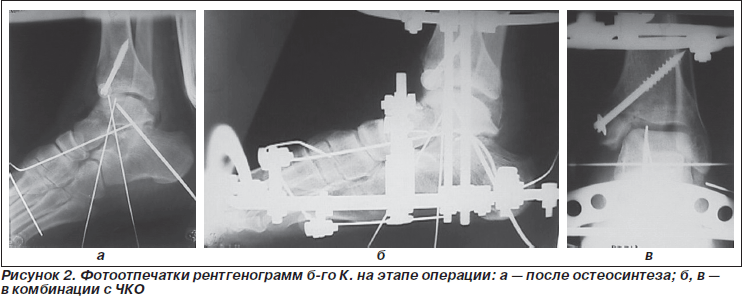

Репозиция подтаранных вывихов производилась закрыто. В 4 случаях оперативный доступ к таранной кости проходил через имеющийся перелом внутренней лодыжки с последующим ее остеосинтезом шурупом или винтом-шилом ЦИТО. Во всех остальных случаях имела место открытая репозиция латеральным доступом или через имеющуюся рану. Для лучшей визуализации фрагментов пересекались сухожилия малоберцовых мышц. Отломки фиксировались отрезками спиц Киршнера или тонкими шурупами.

Разработанная нами методика оперативного лечения предполагает открытую анатомическую репозицию фрагментов таранной кости, остеосинтез переломов шурупами или спицами (как с выведением их на кожу, так и в погружном варианте) и чрескостный остеосинтез аппаратом спице-стержневого типа. Особенностями последнего является то, что внешняя конструкция состоит из двух модулей на голени и на стопе. В раннем послеоперационном периоде модули жестко соединены резьбовыми штангами, что позволяет контролировать величину дистракции в голеностопном и подтаранном суставах, а также обеспечить функцию опоры на конечность в аппарате. С 4–5-й недели производили смену жесткой фиксации между модулями АВФ на шарнирную с сохранением умеренной дистракции. Шарниры центрировались в оси вращения голеностопного сустава, что позволяло обеспечить пациенту активные и пассивные движения в нем. Возможность таких движений обеспечивалась демпфер-системой из резинового жгута и жесткого подстопника со стелькой-супинатором для формирования свода стопы.

Больной К., 34 года, поступил в клинику НИИТО в ургентном порядке по поводу закрытого оскольчатого центрального переломовывиха таранной кости (тип IV), оскольчатого перелома внутренней лодыжки слева со смещением. Травма в результате ДТП. Больной, водитель легкового автомобиля, доставлен СМП с транспортной иммобилизацией. В ургентном порядке выполнена операция: открытая репозиция переломовывиха таранной кости из внутреннего доступа через линию перелома внутренней лодыжки с остеосинтезом спицами и винтом, в комбинации с чрескостным остеосинтезом. Послеоперационный период без особенностей, рана зажила первично. Диафиксационные спицы удалены через 5 недель, установлены шарниры, разрешена осевая нагрузка и разработка движений. Фиксация в АВФ в течение 3,5 месяца. Консолидация достигнута, анатомо-функциональный результат удовлетворительный.